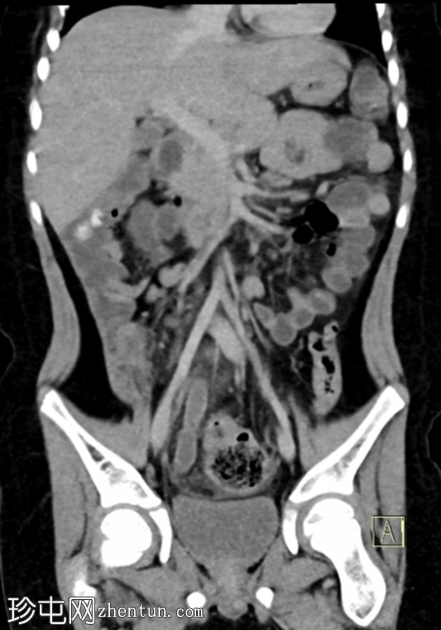

冠状位增强扫描(门静脉期)

阑尾充血膨胀,直径10 mm,轻度壁增厚及强化,周围脂肪间隙模糊。

回盲部及阑尾开口轻度壁增厚,可能为炎症性增生(回结肠炎)。

右髂系膜淋巴结肿大。

该病例的影像学表现符合急性阑尾炎的典型特征,表现为阑尾充血膨胀(最大直径10 mm),轻度壁增厚及强化,周围脂肪间隙模糊。

本病例的其他发现包括右髂窝肠系膜淋巴结肿大(反应性增生)和回盲部肠壁增厚,这可能代表反应性肠壁增厚(继发于阑尾炎),但更可能在本病例中,是炎症/感染(回结肠炎)的早期阶段,最终扩散至阑尾开口,导致阑尾开口管腔狭窄,进而发展为急性真性阑尾炎——本病例中未见阑尾粪石阻塞阑尾开口。